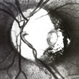

- nerve, optic nerve pit, visual field defect, Humphrey visual field, amblyopia, hemifield

- Kim Barrett C.O.A. Retina Specialist of Michigan, Grand Rapids, MI

Fundus camera

Optos California - Description

- A 14-year-old male presented with vision loss and VF defect. Patient was treated for presumed amblyopia with patching since age 4. He has had neurologic care for post traumatic skull fracture and brain bleed in 2012. Patient has a superior hemifield defect OS on HVF. IOP's WNL. There are vessels emanating from the optic pit OS. Patient is at risk of serous detachment. Current VA 20/20-2+2